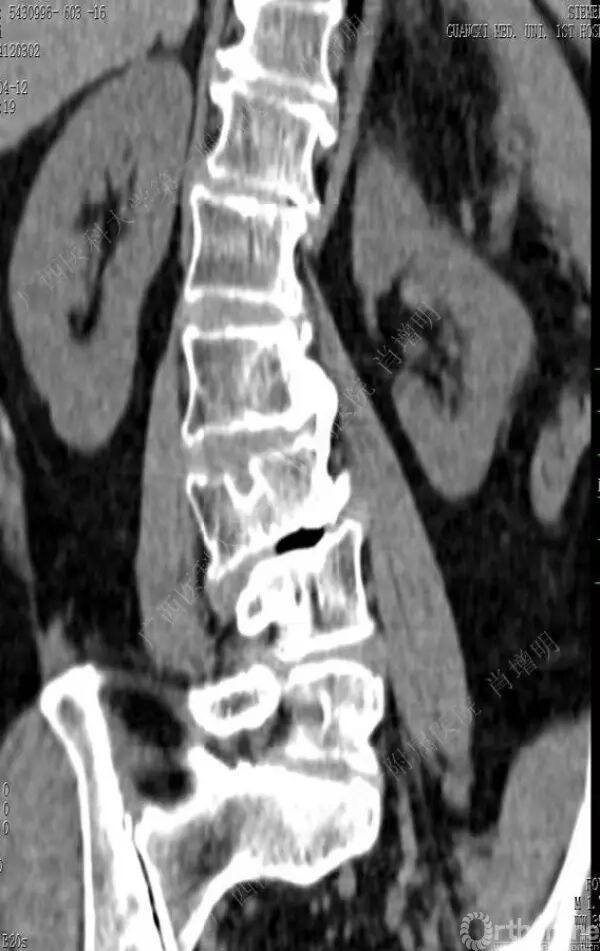

退变性脊柱侧凸是由于椎间盘退变后继发小关节退变,椎管和神经根管容积变化以及脊柱失稳,畸形等病理改变,以疼痛和神经压迫症状为主要表现的常见疾病。

退变性脊柱侧凸多发于50岁以上的中老年群体,是现代常见的老年疾病。多年来,针对该病的临床研究一直没有停步,广西医科大学第一附属医院肖增明教授细致地介绍了该病的诊疗进展。